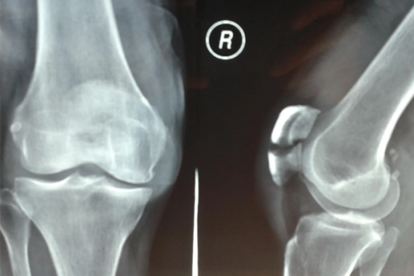

髌骨骨折韧带断裂症状有哪些

髌骨骨折韧带断裂的症状主要有膝关节疼痛肿胀、活动受限、关节不稳、皮下淤血以及关节弹响或交锁。髌骨骨折韧带断裂可能与外伤、运动损伤、骨质疏松、韧带退行性变、关节炎症等因素有关,通常表现为膝关节功能障碍、局部压痛、异常活动等症状。

髌骨骨折韧带断裂后应保持患肢制动,使用拐杖辅助行走避免负重。饮食上应增加富含钙质和蛋白质的食物如牛奶、鱼肉、豆制品,有助于骨骼修复。康复期间避免剧烈运动和重体力劳动,遵医嘱进行关节活动度训练和肌肉力量练习。定期复查X线或核磁共振评估愈合情况,出现发热、持续肿胀或疼痛加剧应及时就诊。